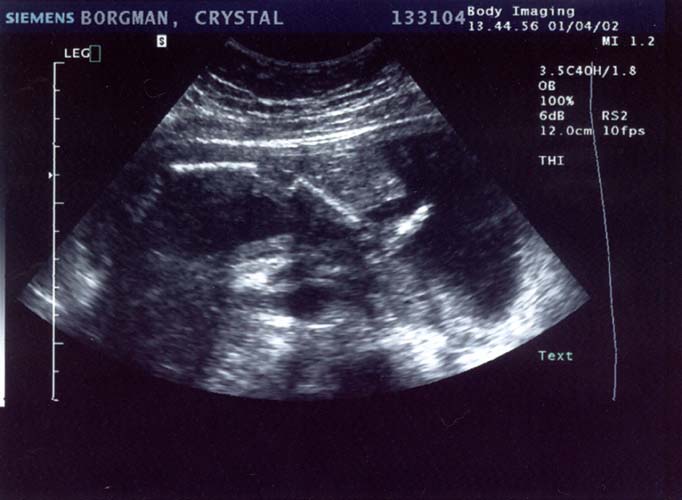

1/4/02

20 weeks

Well

it's a stubborn little bugger. The ultrasound technician

tried and tried so hard to find out the sex, bless her

heart. At the beginning she thought maybe she saw something

that would indicate it was a boy, but she wasn't even

remotely sure by any means. She said she'd check again

later and wasn't confident in the least bit that it was

actually a boy.

Later came, and

went. Baby had its legs crossed the whole time. She

also said there was a lot of umbilical cord around the

legs, so what she saw earlier may have been the cord

too. I drank a full 12 ounces of Coke before I went

in, hoping that would get the baby moving. It was moving

alright, but apparently not enough. The tech tried pushing

on my belly at all angles to get the baby to move but

it would not budge. Well I have to say I'm pretty bummed.

I've been holding out on buying clothing and stuff...

but now I know what I need to get: a whole shit-load

of gender neutral stuff. No, we will not be getting

another ultrasound so this is it until the baby's born.

On a happier note,

everything checks out ok. We saw 4 chambers in the heart

and it was beating away happily at about 142 bpm, she

said. All organs appeared to be present and looking

good. The big shocker was that the estimated weight

was 1 pound, 11 ounces. OUCH! All my pregnancy calendars

say it should still be under a pound... but maybe their

estimate was off. That does, however, help explain my

6-pound weight gain in the last month. At any rate,

all the measurements were normal and my due date remains

unchanged.

Ultrasound Pictures:

Profile with head

on the right, facing down (towards my back), spine clearly

visible

Large

- 663x550 pixels / 66.1K

Small

- 332x250 pixels / 28.2K

Leg (foot is on

the right, pointing up)

- 682x500 pixels / 68K

- 341x250 pixels / 28.8K